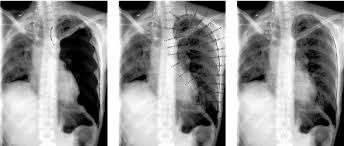

DELIMITACIÓN DE PULMÓN

ROIs campo pulmonar

Son áreas rectangulares que rodean,

lo más cerca posible, cada campo de pulmón.

El método propuesto para localizar estas áreas se basa en la proyección de áreas de imagen rectangular, a partir de direcciones horizontal y vertical.

Para extraer las forneras del pulmón se siguen una serie de pasos

Detección de píxeles del borde del mediastino y costales

Detección de la parte superior e inferior de los píxeles

Eliminación de píxeles del borde periférica

Combinación de píxeles para definir un contorno cerrado

campos de limitación del pulmón

primera fase: dos regiones rectangulares de interés

(ROI) se determinan

segunda fase, los ROI se analizan con el fin de

obtener una ubicación precisa de los límites de pulmón